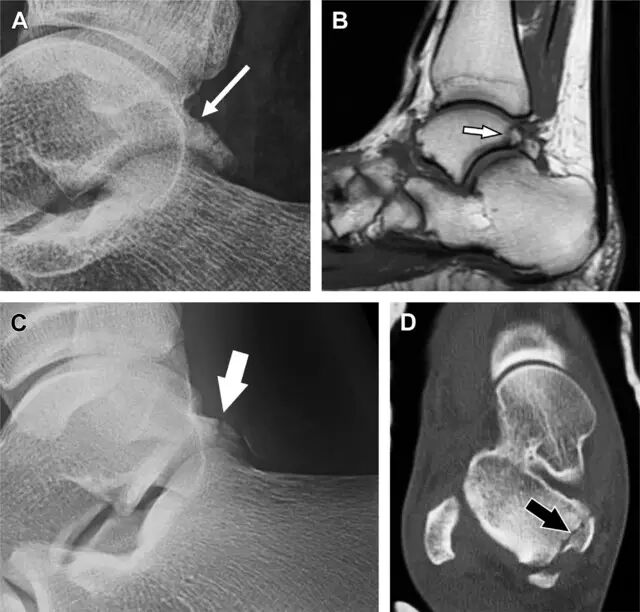

涉及到三角韧带和外侧副韧带(LCL)的复杂性骨折常常不难发现,尤其是存在表面软组织肿胀时。然而,后胫腓韧带牵拉引起的胫骨后踝骨折则很难发现。这些骨折大小不一(图 2),却很重要,因为他们常与胫骨远端螺旋骨折有关,或者是三踝骨折的一部分。

图 2 胫骨后踝骨折。A 侧位片示来源于胫骨后踝的一个小骨折碎片(箭头),因踝部扭伤导致;B 另一位跖屈损伤的患者,侧位片示一个大骨折块(箭头)